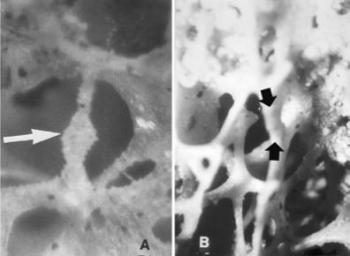

48. ábra. a) Resorptiós terület (nyíl) osteoporosisos csontgerendán. SEM 400× nagyítás b) Gömbszerű callussal gyógyult (nyíl) microfractura. SEM 110× nagyítás. Mindkettő senilis korú nő ágyéki csigolyája